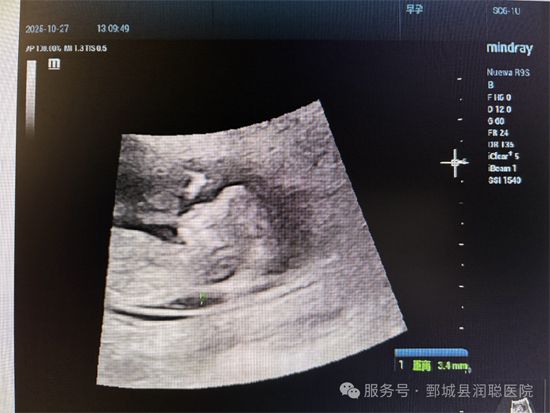

测量游标必须垂直于胎儿皮肤,放在透明层的zui宽处,轻微移动游标只能改变0.1mm的 读数,多次测量后取zui大值。

正常范围:NT值通常不超过3.0mm,数值随孕周增加会略有上升,但只要在正常区间内就无需过度担心。